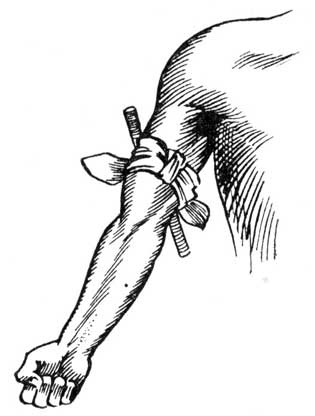

Preparing Blanket for Fomentation.